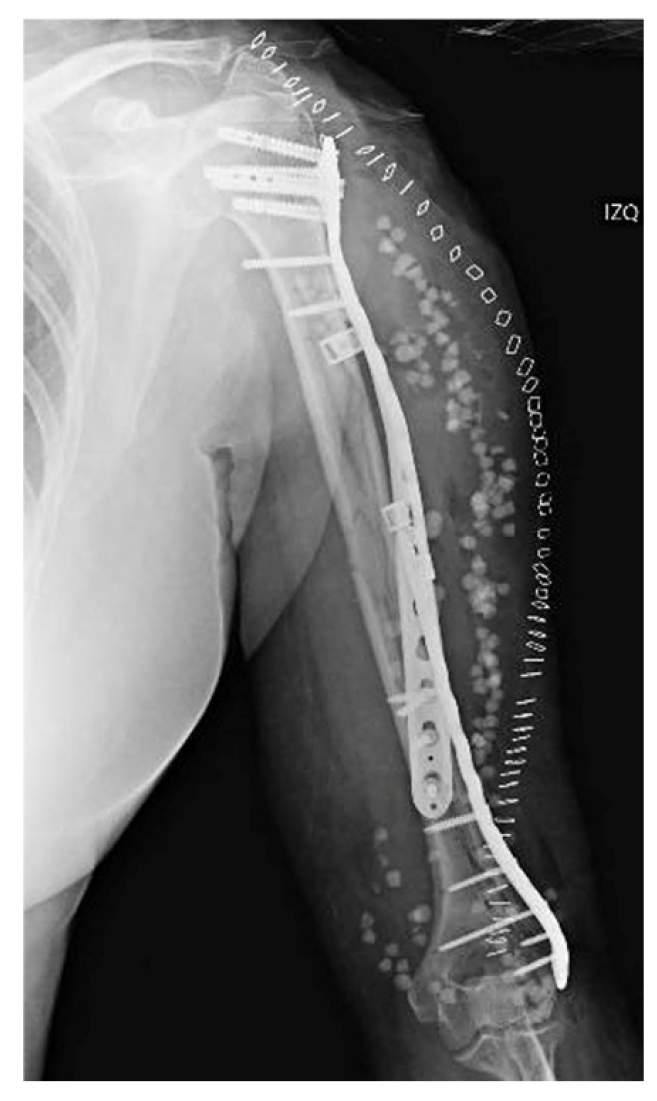

Two weeks after surgery, the patient achieved 100° flexion and −15° extension, without any kind of secondary displacements being radiographically apparent. At three months, X-rays demonstrated that healing was progressing satisfactorily, with the patient exhibiting a normal range of motion. The 6-month radiographs showed complete healing of the fracture, with the physical exam revealing a full range of motion. At one year from the procedure, function was assessed by means of the Disabilities of the Arm, Shoulder and Hand (DASH) scale and the Mayo Elbow Performance Score (MEPS), in which the patient obtained scores of 86 and 75 points, respectively (Figure 5). Simultaneously, the patient was referred to Rheumatology due to a low-energy fracture and a history suggestive of bone fragility. Osteoporosis was confirmed, and treatment with calcium, vitamin D, and antiresorptive therapy was initiated.

Figure 5. Radiographic follow-up at 6 months post-op.